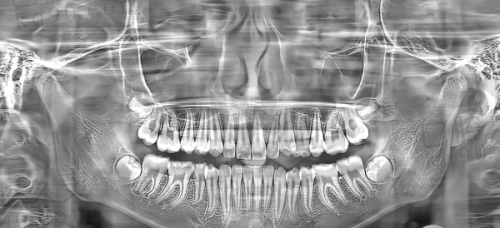

有人可能会担心私立医院的医疗服务质量。然而,娄底协合口腔医院在医疗服务质量上并不逊色。医院招聘了一批经验多、技术不错的口腔医生。这些医生大多毕业于有名的口腔医学校校,并且具有多年的临床工作经验。医院还注重 医生的继续教育和培训,定期组织医生参加国内外的学术交流活动,不断提升医生的专精水平。在医疗设备方面,医院引进了精良的口腔诊疗设备,如数字化口腔全景机、种植机等。这些设备能够为医生的诊断和治疗提供更加正确的依据,提高治疗成效。所以,虽然娄底协合口腔医院是私立医院,但在医疗服务质量上是有保护的。